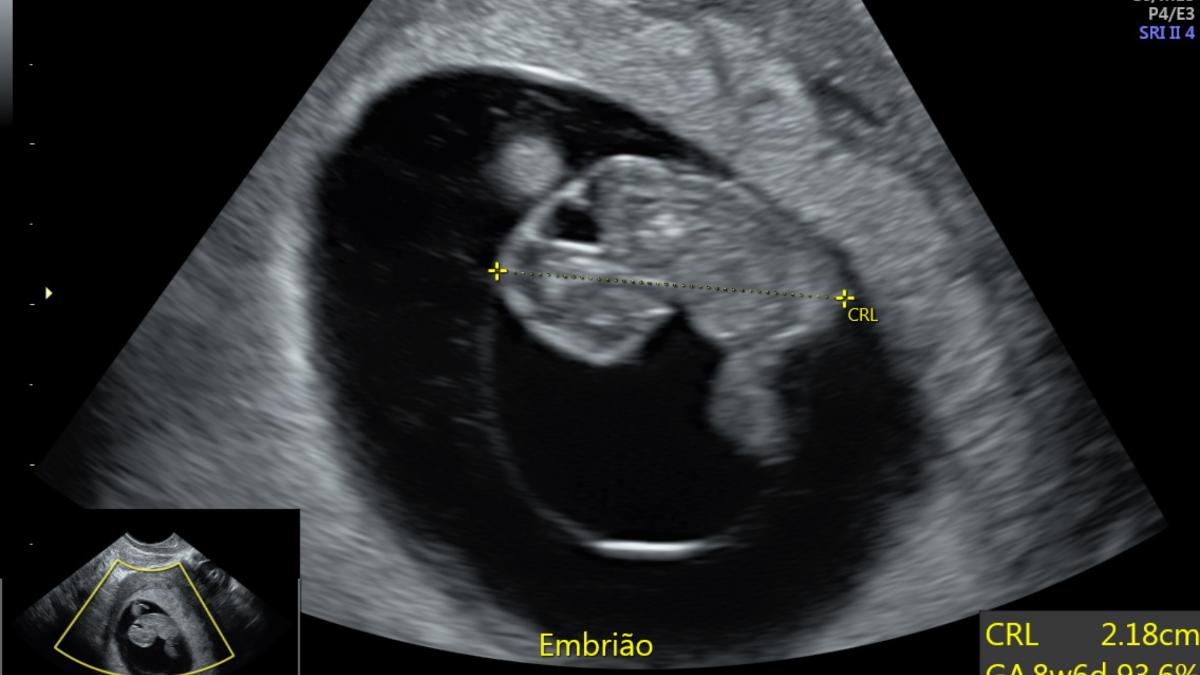

Mas o que as pessoas às vezes não sabem, é que existe um momento ideal para realizar esse primeiro ultrassom, que é com 7 semanas. Nesta idade gestacional, o embrião está com 10 mm de comprimento cabeça nádega (CCN), que é o jeito que usamos para medir os bebês até 14 semanas.

É nessa data, por volta de 7 semanas, que a margem de erro do ultrassom para o cálculo da idade do embrião é menor, e é por isso que esse é o melhor momento para fazer esse exame.

É possível identificar batimentos cardíacos embrionários desde que o embrião é bem pequeno, as vezes quando ele tem somente 2 mm de comprimento. Com 6 ou 7 semanas, o mais comum é que já seja possível ouvir no ultrassom o coração do bebê. Essa capacidade de identificar batimentos bem no começo da gestação, em embriões bem pequenos, depende de vários fatores, sendo a qualidade da máquina de ultrassonografia uma das principais.

Com 5 semanas e meia a 6 semanas é possível enxergar o bebê no exame ultrassonográfico, que aparece como um grãozinho branco grudado na vesícula vitelínica. Conforme ele cresce, podemos identificar os batimentos do coração do embrião.

Embrião – 8 semanas

Toda gravidez segue esses passos de desenvolvimento normal no início. Como nosso objetivo nesse primeiro ultrassom na gravidez é ver e medir o tamanho do bebê, o ideal é que realizemos esse exame quando o bebê já é claramente visualizado e com batimentos cardíacos presentes. Isso é mais garantido a partir de 7 semanas.